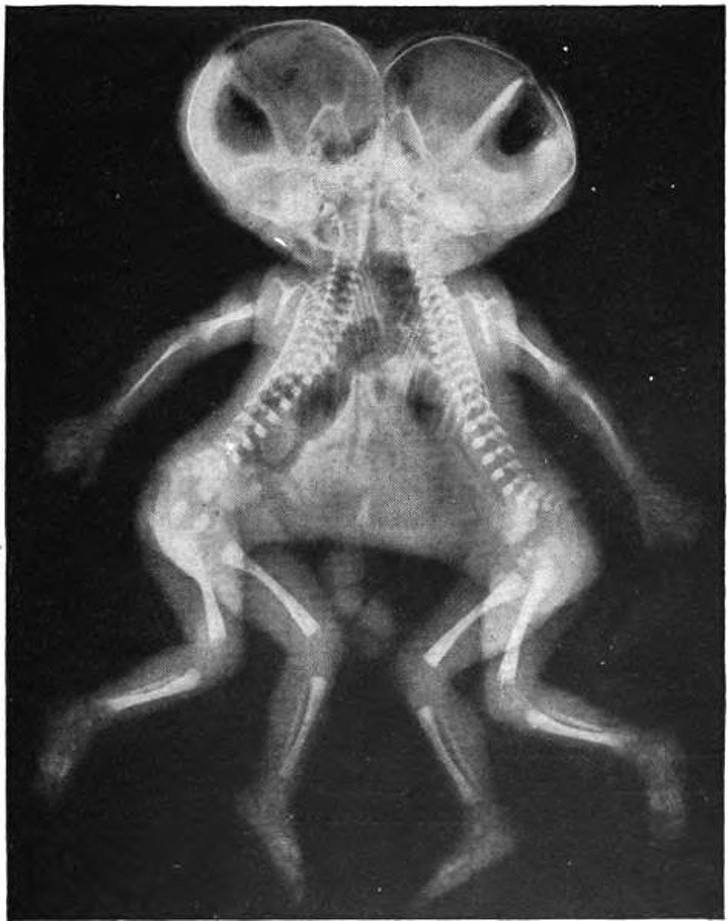

Humans are truly strange creatures and incredibly bizarre things can happen to us. These x-rays will shock even those who think they've seen it all.

Radiologists are already quite accustomed to seeing on X-rays strange things and some of these that we have collected for you in the gallery did not surprise them at all. Here is 15+ hacked and sometimes shocking x-rays.